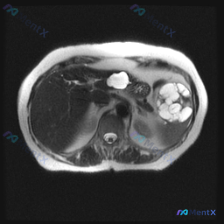

影像核心表现(T2加权轴位)

- 肝脏:信号无明显弥漫或局灶异常

- 脾脏:可见类圆形多房性囊性病灶,边界清晰,T2呈显著高信号(符合囊液信号),无周围浸润或水肿带

- 上腹部额外发现:胰腺体尾部前方/胃后方,还有一个孤立的、边界清晰的类圆形高信号囊性灶

- 其他:无腹水,大血管、脊柱旁软组织结构无明显异常